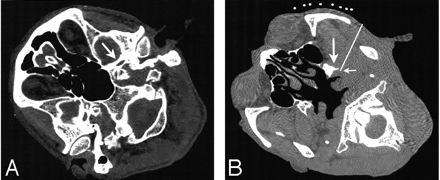

Following sterilization and administration of a subcutaneous anesthetic of 0.5% lidocaine, a KT TFW 22-gauge, 97-mm guiding needle (Hakko, Inc, Tokyo, Japan) was inserted from the marked point. The insertion angle of the needle was adjusted by using the red-colored guiding laser of the CT gantry, which conformed to the scanning section. The needle was then advanced following the predetermined route under real-time CT fluoroscopy. When the needle tip was located at the target site (Fig 2), low-voltage sensory stimulation was applied with a lesion generator (0.1–0.2 V at 50 Hz, RFG-3CF, Radionics, Burlington, Mass) to ensure that electric stimulation reproduced the pain in the diseased area. Motor stimulation (0.1–0.2 V at 2 Hz) was then applied to verify proper electrode placement. Contractions of the masseter muscle were observed with the electric stimulation when the electrode was properly placed. Thereafter, the effect of nerve block was simulated by a test dose injection (2% mepivacaine hydrochloride, 0.3 mL). After confirming the loss of sensation at the diseased area and the lack of side effects, we performed denervation by applying radio-frequency current by using the RFG-3CF lesion generator. Electrocoagulation was performed at 90°C for 90 seconds. The CT fluoroscopy used in our case radiated 0.176 mGy/s (10 mA, 120 kV, per 3-mm section). The patient did not have severe discomfort during the procedure.

The needle tip is located at the target site of the mandibular nerve.